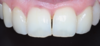

Prévisualisation du futur sourire

Prévisualisation du futur sourire. Cas clinique 4 : simulation de pose de facettes céramiques sur les incisives latérales.